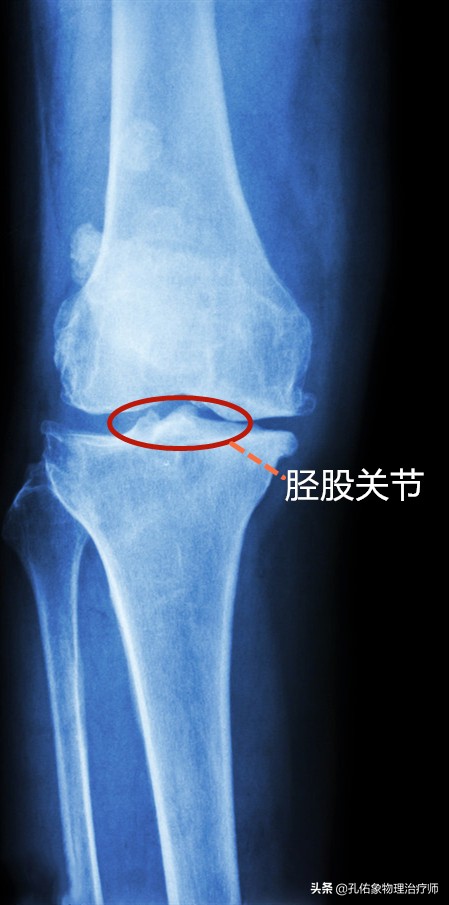

构成人体膝关节复合体之一的关节,就是上图所示的大腿骨与小腿骨连接的胫股关节,若是拍片后,它是长这样的,看下图:

X片胫股关节

髌股关节

另一个构成人体膝关节复合体之一的关节,就是上图所示的大腿骨与膝盖骨连接的髌股关节,若是拍片后,它是长这样的,看下图: